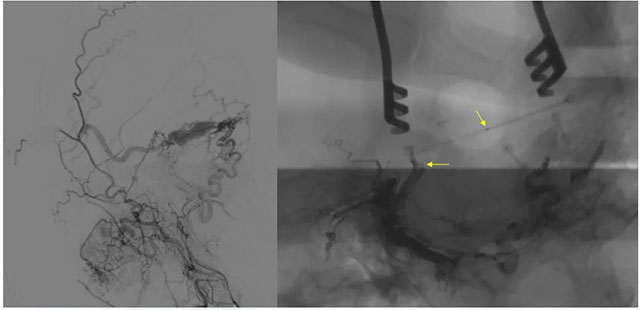

▲ 術(shù)前定位

8月23日,在復(fù)合手術(shù)室,在長(zhǎng)海醫(yī)院方亦斌教授指導(dǎo)下,張琪博士根據(jù)之前造影手術(shù)標(biāo)記點(diǎn)確定平行左側(cè)外耳道手術(shù)切口約 8cm,切開頭皮各層至顱骨,剝離骨膜,牽開,以咬骨鉗咬開一約 3cm 缺口,充分暴露橫竇。

▲ 造影確認(rèn)位置后,穿刺左側(cè)橫竇,置入 Echelon10 微導(dǎo)管

▲ 再次造影確認(rèn)位置后,填入 HELIX 6/20彈簧圈

▲ 微導(dǎo)管造影確認(rèn)后,注入 Onyx 18膠 5ml

經(jīng)左側(cè)股動(dòng)脈以單彎造影管超選至左側(cè)頸總動(dòng)脈造影明確靜脈穿刺點(diǎn)入路,予以穿刺針穿刺成功后造影明確在位,隨后 Echelon 10微導(dǎo)管到位橫竇,填入一枚彈簧圈做塞子,造影明確位置后,緩慢注入 Onxy18膠 5毫升,鑄膠彌散良好,通過靜脈逆向彌散至部分供血?jiǎng)用}內(nèi)。復(fù)查造影,見瘺口完全被栓塞,引流靜脈消失,手術(shù)成功。